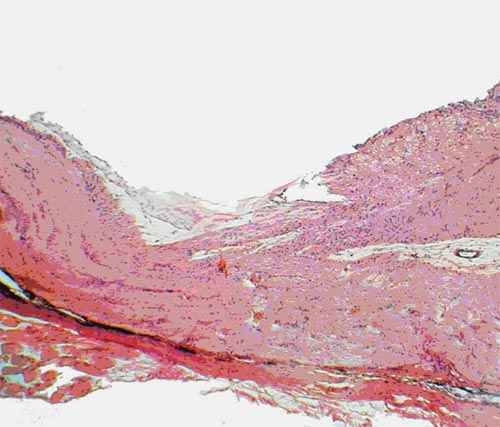

У группы интактных животных (№ 1) проведенные собственные исследования позволили выявить, что в назальной половине сетчатки глаза количество ганглиозных клеток на 20-30% больше, чем в височной половине. В этой группе в обеих половинах сетчатки в слое фоторецепторов и биполяров по направлению к углу задней камеры глаза наблюдалось уменьшение толщины слоев и количества клеток. Обнаружено, что количество крупных клеток в группе интактных животных больше при приближении к цилиарному телу, а мелких - к диску зрительного нерва. В группе интактных животных (№ 1) в ганглиозном слое располагались клетки с ядрами различных размеров. Цитоплазма клеток имела слабо эозинофильную окраску, ядра хорошо прокрашивались гематоксилином в синий цвет (рис. 1).

Интактные кролики. Обычное содержание клеток в сетчатке: 1 - ганглиозный слой, 2 - слой биполярных клеток. Окраска гематоксилином и эозином. Ув.  200

Рис. 1. Интактные кролики. Обычное содержание клеток в сетчатке: 1 - ганглиозный слой, 2 - слой биполярных клеток. Окраска гематоксилином и эозином. Ув. 200

Количество их распределялось следующим образом: всего клеток - 509,67±12,35, из них: мелких - 184,00±5,00; средних - 229,17±12,41; крупных - 96,50±3,58. В норме соотношение: мелкие/средние/ крупные клетки было 36/45/19%. Толщина слоя аксонов ганглиозных клеток при измерении на расстоянии 350 мкм от края решетчатой пластинки, где ход аксонов был еще параллельным сетчатке, равнялась 129,15±1,86 мкм. Слой имел равномерное слабо розовое окрашивание, на его поверхности лежали тонкостенные капилляры (рис. 2).